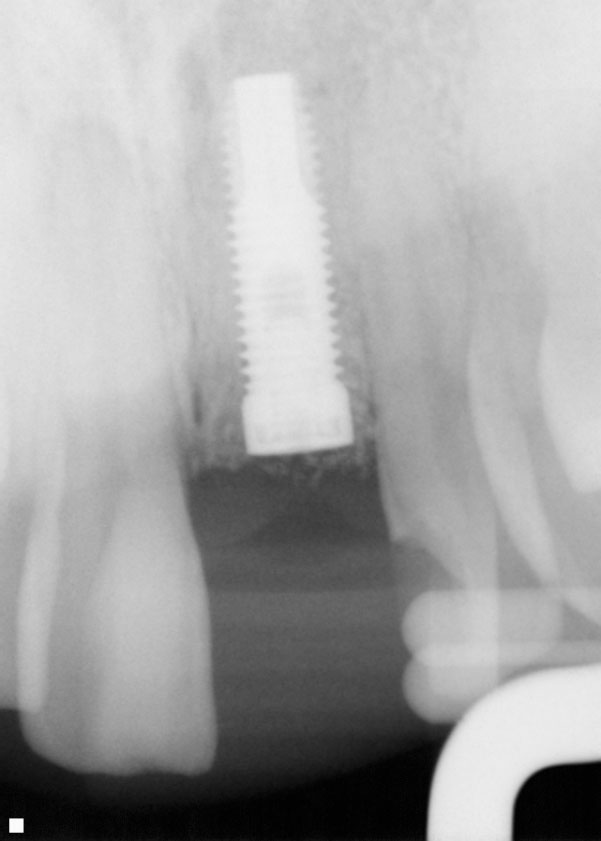

Din cele 109 implante inserate la cei 69 pacienţi în cursul unei perioade de 4 ani, nu s-a înregistrat niciun eşec implantologic după inserţia dispozitivelor fixe şi restaurarea protetică ulterioară. La descoperirea implantelor, nu erau semne de mobilitate a acestora, şi toate implantele inserate au fost restaurate. În momentul prelucrării datelor, toate implantele au rămas complet încărcate şi în funcţiune, rezultând o rată de supravieţuire de 100% (tabelul 1). Ca şi grup, implantele erau funcţionale şi încărcate de o perioadă medie de 2 ani, variind între 6-65 luni. Indiferent de tipul implantului, localizarea în alveolă, statusul de fumător, 100% din implante sunt în funcţiune şi actualmente (tabelul 1 şi fig. 1-9).